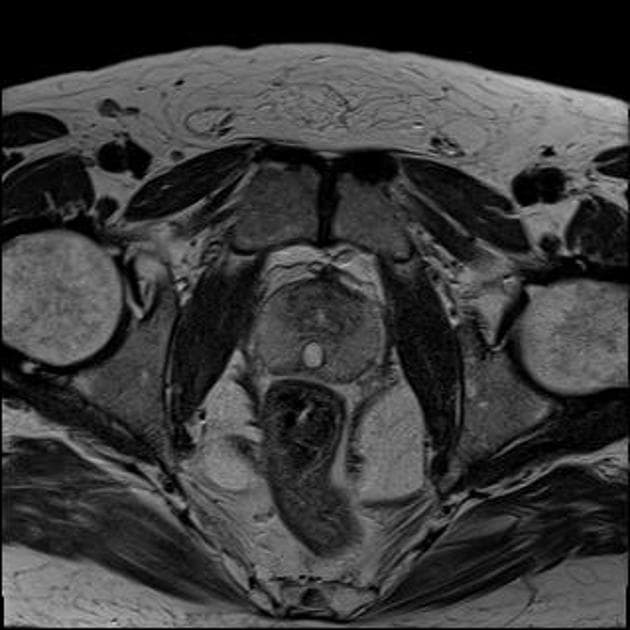

Axial t1_vibe_dixon_post_W

- Có một tổn thương dạng nang (cystic lesion) giới hạn tương đối rõ (well defined), nằm ở đường giữa (midline), phía sau bàng quang (bladder) tại vùng tuyến tiền liệt.

- Tổn thương tăng tín hiệu (hyperintense) trên các hình ảnh T2W và không thấy tăng quang (no enhancement) trên phim chụp T1W sau tiêm thuốc tương phản (post contrast scan).

- Nang mở rộng lên trên đến giữa các túi tinh (seminal vesicles), có hình quả lê (pear-like shape) và không thấy sự thông thương rõ ràng với niệu đạo (urethra).

- Đồng thời ghi nhận có ít mô tuyến tiền liệt (prostatic tissue).

THẢO LUẬN (DISCUSSION): Tổn thương dạng nang (cystic lesion) ở đường giữa vùng tuyến tiền liệt, mở rộng lên phía trên tuyến tiền liệt, không thông thương với niệu đạo, gợi ý (suggestive of) nang ống Mullerian (mullerian duct cyst).